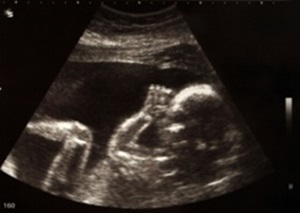

3d ultraschall baby hasslich. Ein 3DUltraschall ist für viele werdende Eltern ein sehr emotionaler Termin während der Schwangerschaft Sie können ihr Kind zum ersten Mal richtig sehen Doch diese Zusatzleistung der. Frau Christine Beerli besitzt jahrelange Erfahrung im 3D/4D Ultraschall Mit viel Geduld und Können gelingt es ihr, Ihnen wunderschöne Bilder und bewegende Einblicke ihres Kindes bereits in der Schwangerschaft zu ermöglichen und als Erinnerung mit nach Hause zu nehmen. Durch den 3DUltraschall erhalten wir eine räumliche Darstellung Ihres Babys Bei guten Schallbedingungen können wir so praktisch die ersten Fotos des ungeborenen Kindes anfertigen Beim 4DUltraschall sehen Sie am Ultraschallmonitor ein ständig aktualisiertes dreidimensionales Bild, in dem sich alle Kindsbewegungen in Realzeit darstellen.

Von Silke R Plagge Die Vorfreude war riesig In der 18 SSW endlich das große 3DUltraschallbild Doch dann kam das Entsetzen Im Bauch ist ein Alien!. Obwohl zahlreiche Studien belegen, dass ein korrekt und von einem erfahrenen Spezialisten durchgeführter 3D/4DUltraschall nicht gefährlicher ist als ein herkömmlicher Ultraschall, soll das beliebte „BabyFernsehen“ ab 21 verboten werden und nur noch unter bestimmten Voraussetzungen erlaubt sein. Der 3DUltraschall, auch "Babyfernsehen" oder "BabyKino" genannt, ist eine Methode, bei der gestochen scharfe Bilder und Videos des ungeborenen Babys im Mutterleib erzeugt werden.

1811 1730 Uhr Cheyenne Ochsenknecht „Ich habe immer ein großes Grinsen im Gesicht“ Zeitgleich mit der Erscheinung ihres ersten Buches ließ Cheyenne Savannah Ochsenknecht die Baby. Für werdende Eltern ist es ein emotionaler Moment, Ultraschallbilder über große Bildschirme im 3DUltraschall zu sehen Das sogenannte "BabyTV" boomt Doch ab 21 ist das für solche nicht. Beim 3DUltraschall werden die Bilder dreidimensional auf den Bildschirm gesendet, wodurch deutliche Bilder von Ungeborenen möglich werden die insbesondere Laien auch gut erkennen könnenDie Ultraschalldiagnostik des Arztes kann in Einzelfällen durch die zusätzliche Einbindung der 3DTechnik zusätzliche Informationen geben.

Re Angst dass meinBaby hässlich wird Antwort von Mörchen17 am 1504, 2333 Uhr Bei der Feindiagnostik in meiner Schwangerschaft diagnostizierte die Ärztin eine "auffällige Kopfform" bei meinem Kind und ich habe mich ab da auch gefragt, ob ich nun ein "Ungeheuer" bekommen werde schlussendlich war es einfach ein supersüßes Baby ohne irgendwelche Auffälligkeiten im Kopfbereich. Von Silke R Plagge Die Vorfreude war riesig In der 18 SSW endlich das große 3DUltraschallbild Doch dann kam das Entsetzen Im Bauch ist ein Alien!. Ultraschall in 3D erlaubt lebensechte Bilder von Ihrem Baby schon während der Schwangerschaft Im Grunde funktioniert ein Ultraschallbild in 3D nach einem ähnlichen Prinzip wie in 2D Mittels Schallwellen und dem davon zurückgeworfenen Echo errechnet der Sonograph die Entfernung des Gewebes von der Körperoberfläche.